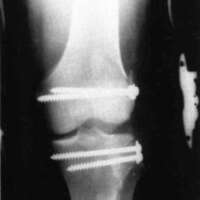

A nineteen year old male sustained a distal fracture with a split condylar fracture to the right leg (Fig. 10) and a lateral condyle fracture on the contralateral side (Fig. 11). Fractures were stabilized, but were not internally fixed at time of admission because of emergency vascular repairs being required. Three days post injury, the patient underwent ORIF of his fractures (Fig. 12 and Fig. 13). The right leg was placed in a free knee Mobilizing Brace and the left leg was placed in the rehabilitative free knee orthosis. A continuous passive motion dynamic suspension system was placed on the lower right extremity (Fig. 14). The lower left extremity had normal pain free motion following surgery. The patient was kept in passive motion for five days and achieved 0-100° of pain free motion. A cast brace was applied on the right extremity; the patient received gait training and was discharged.

Figure 12:

Figure 13: